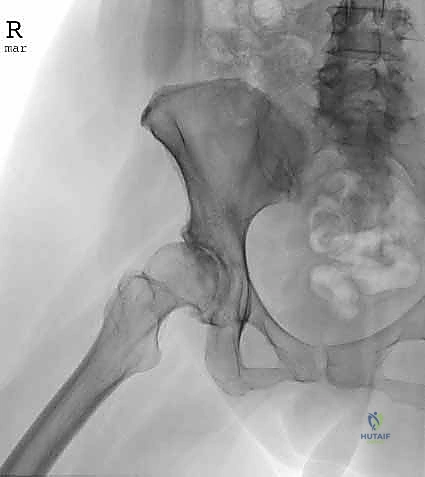

1. الاصطدام الفخذي الحقي (Femoroacetabular Impingement - FAI)

وهي حالة شائعة جداً تحدث عندما تنمو نتوءات عظمية زائدة إما على رأس عظمة الفخذ (Cam) أو على حافة تجويف الحوض (Pincer)، أو كليهما. هذا النمو الزائد يؤدي إلى احتكاك غير طبيعي أثناء الحركة، مما يمزق الشفا الغضروفي ويتلف الغضروف المفصلي.

يقوم الدكتور هطيف باستخدام أدوات دقيقة لنحت هذه العظام الزائدة وإعادة الشكل التشريحي الطبيعي للمفصل.

- الأشعة السينية (X-rays): لتقييم العظام، والتأكد من وجود نتوءات عظمية (FAI) أو علامات مبكرة لخشونة المفصل.